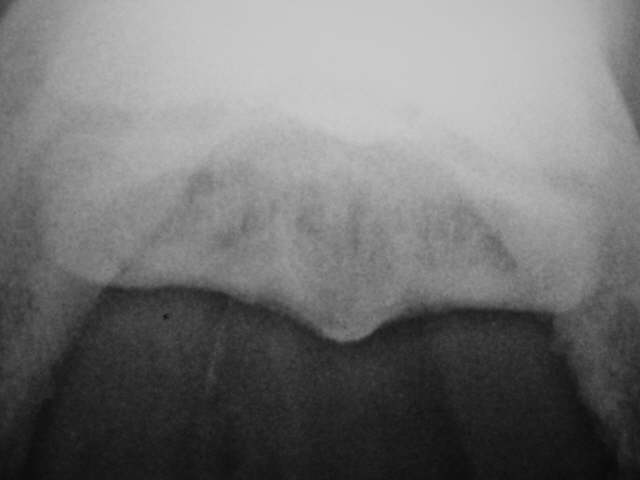

Skyline Befunde

Schlechte Abgrenzung de Knochenschale gegenüber dem Markraum, Verlust der normalen Knochenstruktur mit Sklerosierung und Zystenbildung, unebene Gleitfläche. Röntgenklasse IV